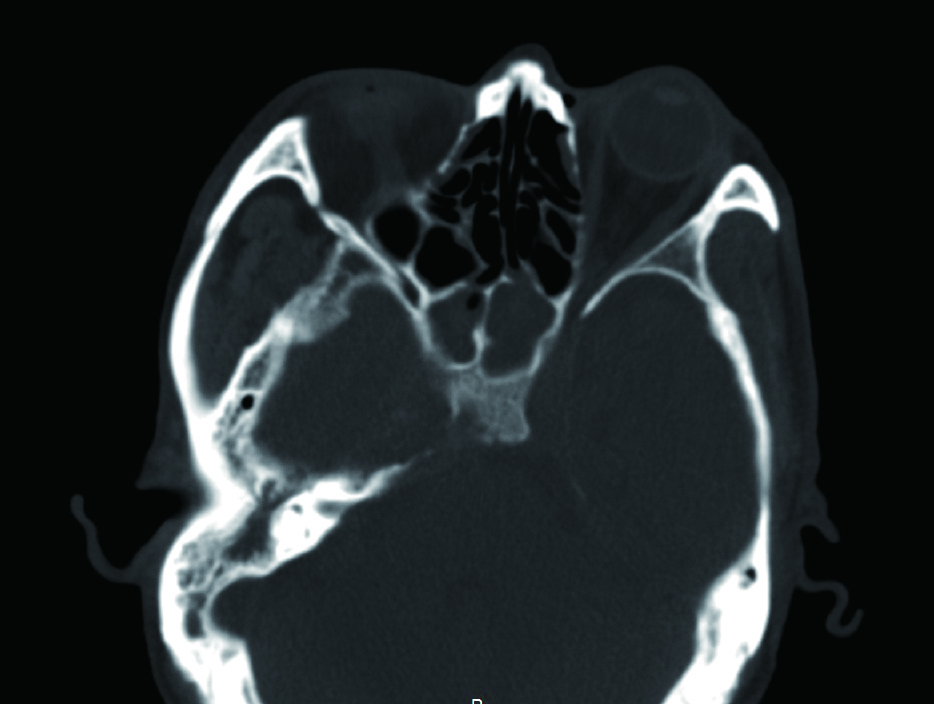

1 资料与方法病例1,患者男性,66岁,因头痛3周,复视1周入院。患者3周前起右侧太阳穴针刺样疼痛,影响睡眠。2周前出现咽痛鼻塞流涕及双耳听力下降,伴有右侧额部皮肤红疹,上述症状在当地医院治疗后减轻。1周前出现复视,当地医院治疗后症状无好转,诊断:颅内感染,多颅神经麻痹转来本院急诊。查体:神清,面部可见散在淡色丘疹,以右侧前额为主,右眼外展受限,面部痛触觉无殊,四肢肌力5级,病理反射阴性。脑脊液生化常规示:潘氏试验阳性,有核细胞970/μL;血沉28.00 mm/h,C反应蛋白14.1 mg/L。增强头颅MR提示两侧海绵窦增粗增宽,考虑炎症,并见双侧筛窦上颌窦蝶窦炎(图 1)。予头孢曲松钠2.0 g静脉注射抗感染治疗。治疗2周后头痛明显减轻,但复视症状无好转。复查血常规正常,C反应蛋白正常范围,血沉28.00 mm/h,脑脊液生化及常规正常范围。复查头颅增强MR提示病变范围较前无缩小。鼻窦CT提示双侧蝶窦炎症较前加重(图 2)。建议患者行鼻内镜下蝶窦手术。患者自觉症状减轻拒绝手术,要求出院。出院后在外院继续头孢曲松钠抗感染治疗。治疗10 d后因头痛复视症状无改善,并出现面颊部感觉减退再次入院。入院后查血常规,C反应蛋白正常,血沉28.00 mm/h,脑脊液潘氏试验阳性,细胞数量继续减少至60/μL。继续抗感染治疗。再次头颅MR及鼻窦CT复查提示海绵窦及蝶窦内病变较前范围增大(图 3),经多学科讨论,转本科行视频内镜下双侧蝶窦开放术。术后第三天鼻腔填塞物完全抽除后头痛症状明显缓解,术后6 d出院,头痛症状消失,复视仍存,出院后继续抗感染治疗,定期门诊复诊,术后6个月,复视症状消失。

| 图 3 蝶窦炎症较前加重 |